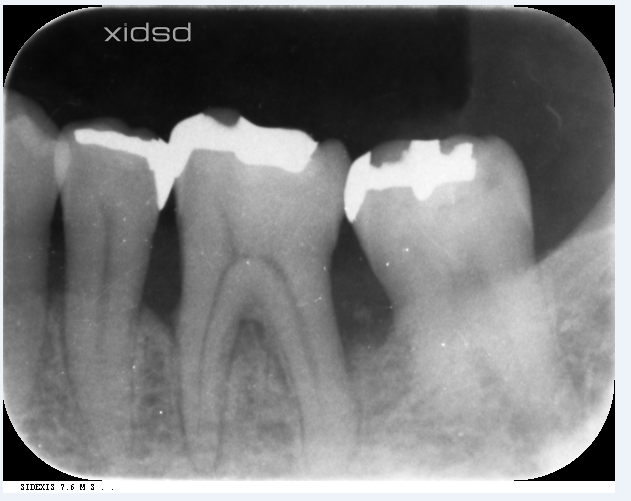

レントゲン

左下の6番の遠心根が根の先の方まで骨がなくなっています。

他院で抜根(後ろの根を抜いていく治療)を勧められたとの事で来院されました・